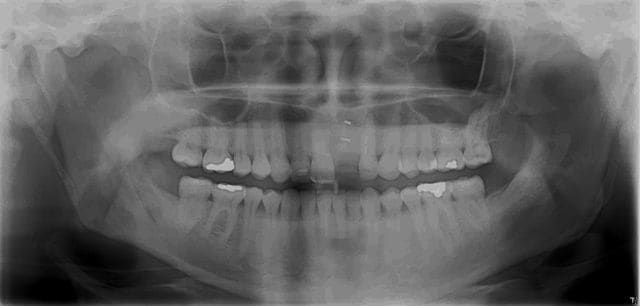

oups j'ai oublié l'OPT avant pdt et la rx après

C'est une reprise de carie sur la 27?

P'etre bien ! Je contrôlerai ça au prochain contrôle mais sur les OPT c'est souvent trompeur